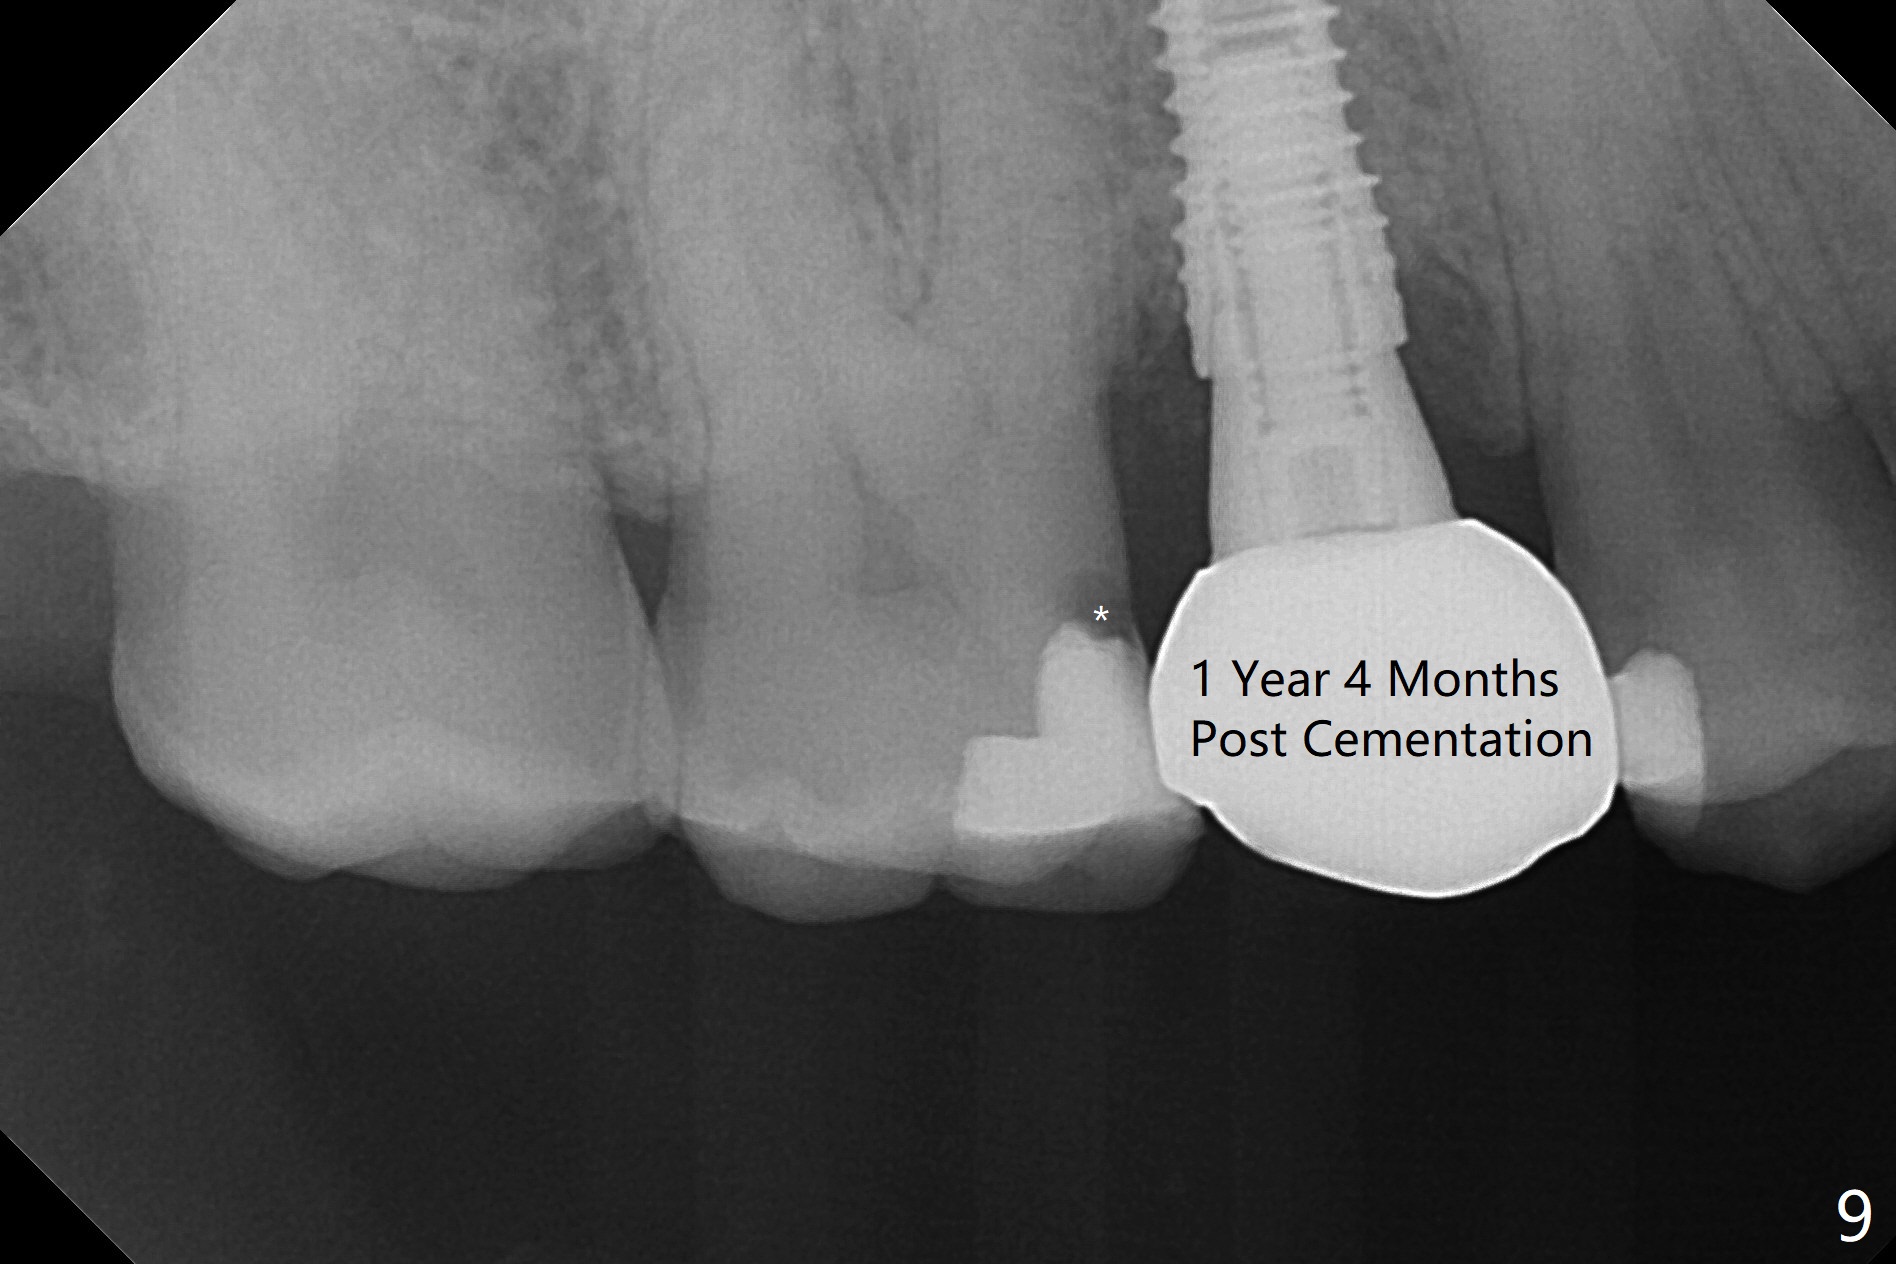

When the tooth #4 with vertical root fracture (Fig.1) is extracted, the buccal plate is found to be lost. The lowest point of the defect is shown as black dashed line in Fig.2 (yellow dashed line: sinus floor). After use of 2.5 mm reamer for 21 mm (buccal gingival level) and 3.0 mm reamer for ~17 mm, a 3.8x15 mm dummy implant is placed with 30 Ncm and 1.85 mm apical space (Fig.3 pink outline). A 3.8x18 mm (definitive) implant is placed with <40 Ncm with the implant plateau apical to the lingual crest (Fig.4,5). The buccal plate defect is repaired by Vanilla Graft (Fig.6 *) before and after insertion of a 4.5x4(3) mm abutment. The buccal plate defect seems to being repaired 4 months postop (Fig.7). Occlusal wear suggests bruxism, which is also associated with the root fracture. Night guard is recommended. The defect repair is close to completion 8 months post cementation (Fig.8). The crown/abutment is found to be loose 1 year 4 months post cementation and retightened without checking whether there is clinical 2nd DO caries of #3 (Fig.9, "sensitive to water pik"). A few days later, DO composite is being removed. It is difficult to determine whether the 2nd DO caries or gap has been removed with the neighboring crown in place. When the crown/abutment is removed and gingival retractions are inserted, there is no decay. The gap is removed. With Toflemire in place, the crown/abutment is reseated and hand tightened; after packable composite, the crown/abutment is removed, there is no more DO gap.

In fact there is a small buccal fistula, which is communicated with the underlying implant threads. Although preop CT shows that the buccal crest is lower than the palatal (3.8x13 mm, Fig.10 P) one, intraop finding of missing buccal plate should dictate a shorter implant (Fig.11) or onlay graft to avoid periimplantitis. Regeneration of the bone plate is limited. Later the fistula disappears with formation of a concavity (Fig.13). There is no symptom. Is bone graft necessary with a remote incision? 3-D images of CT taken 1 year 5 months post cementation show possible mesiobuccal and distopalatal bony defects (Fig.13-16). It is possible that bone graft was placed enough palatal (Fig.16). DO composite at #3 is redo satisfactorily (Fig.17 *).